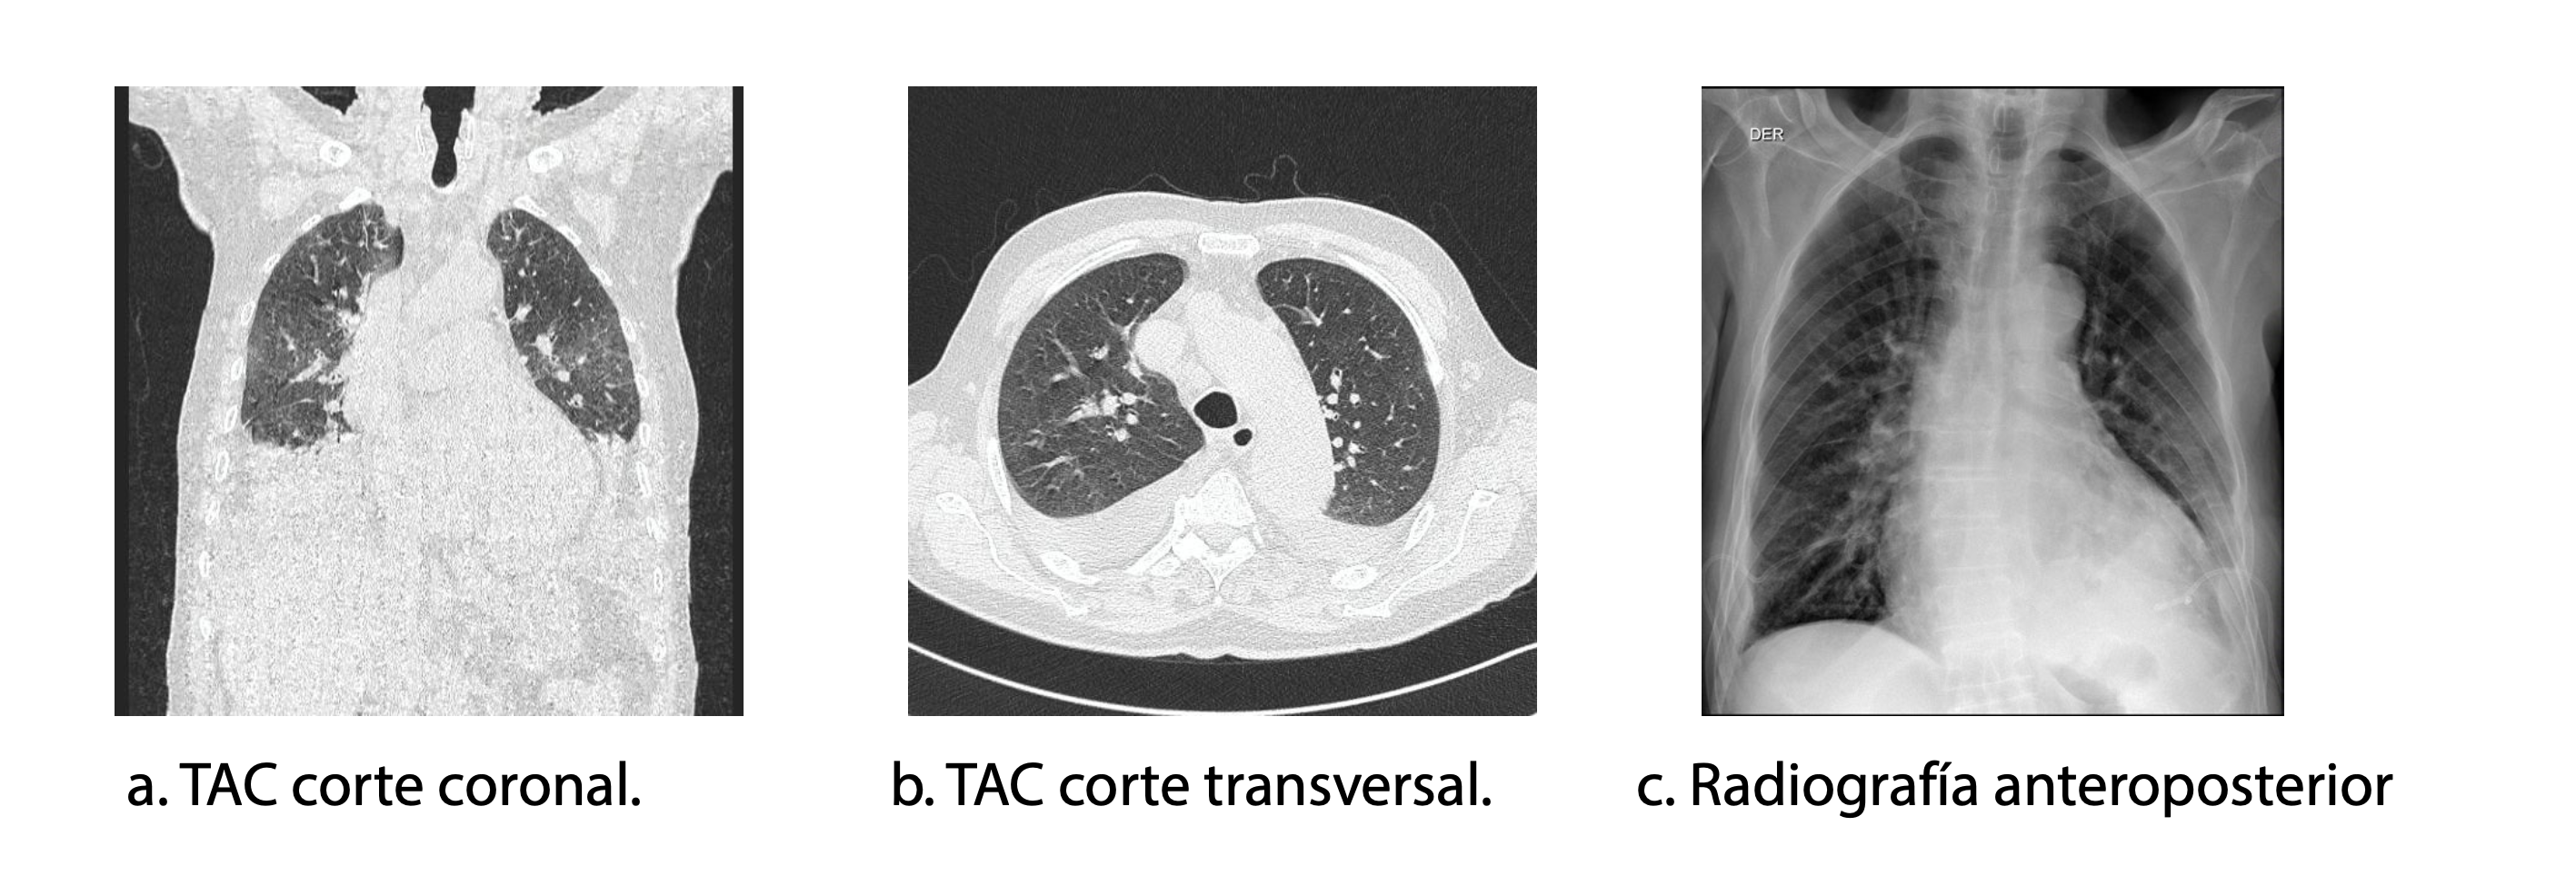

Para el estudio del parénquima pulmonar (Figuras 3a y 3b), se solicitó tomografía axial computarizada de alta resolución de tórax (TACAR) el 01/02/2023, donde se evidenció cardiopatía dilatada, hipertensión pulmonar precapilar, enfermedad arteriosclerótica de arterias coronarias y abundantes derrames pleurales bilaterales, probablemente secundarios a falla cardíaca y sobrecarga hídrica. No se observó neumonía. Se identificaron abundantes ganglios en el mediastino de carácter indeterminado. Debido a los derrames pleurales, se realizó toracentesis diagnóstica y terapéutica, con criterios de trasudado, considerándose su origen en la falla cardíaca (03/02/2023).

Por parte de la coinfección COVID-19 e influenza, se indicó manejo con oseltamivir a dosis de 75 mg vía oral cada 12 horas por 5 días, conforme a las guías IDSA, y se contraindicó el uso de esteroides. El sujeto evolucionó hacia la mejoría (SaO2 96%, FR 16 rpm, FIO2 24%) (Figura 3c), mostrando una evolución clínica favorable. Sin embargo, a pesar de la mejoría, persistía una patología cardiovascular severa que requería intervención. La decisión de someterlo a cirugía cardiovascular fue cuidadosamente discutida en equipo multidisciplinario entre cardiología e infectología, evaluando riesgos y beneficios, considerando la alta probabilidad de complicaciones dado el antecedente reciente de dos infecciones severas. Finalmente, se decidió realizar el procedimiento quirúrgico (TAVI) (09/08/2023). Durante el procedimiento, el paciente presentó paro cardiorrespiratorio y falleció.

Imágenes radiológicas del tórax

Figura 3. Imágenes radiológicas del tórax

Nota: TAC: tomografía axial computarizada.